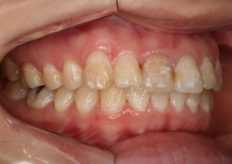

After

並べた歯が前に出ないように歯と歯の間を少しずつ削るIPRを行い治療を行いました、期間は少しかかりましたが綺麗な歯並びになり満足いただけました。